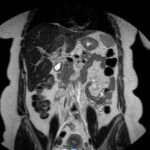

En este caso, presentamos una paciente femenina de 43 años de edad con antecedente de uso de ACO, a quien se le diagnosticó Trombosis portal mediante TC de abdomen c/cte. EV y trombofilia con mutación en el factor II de protrombina 20210, con evolución favorable.

Paciente femenina de 43 años, antecedente de obesidad grado I. Medicación habitual uso de ACO. Antecedente quirúrgico: una cesárea. Presenta cuadro clínico caracterizado por epigastralgia súbita de moderada intensidad. Se automedica con Buscapina sin mejoría del cuadro, por lo que acude a guardia. Le realizan TC y la derivan con diagnóstico de trombosis portal de la rama izquierda.

Se solicita nueva tomografía para descartar progresión de la trombosis y se vuelve a instaurar analgesia y anticoagulación EV.

Hallazgos imagenológicos